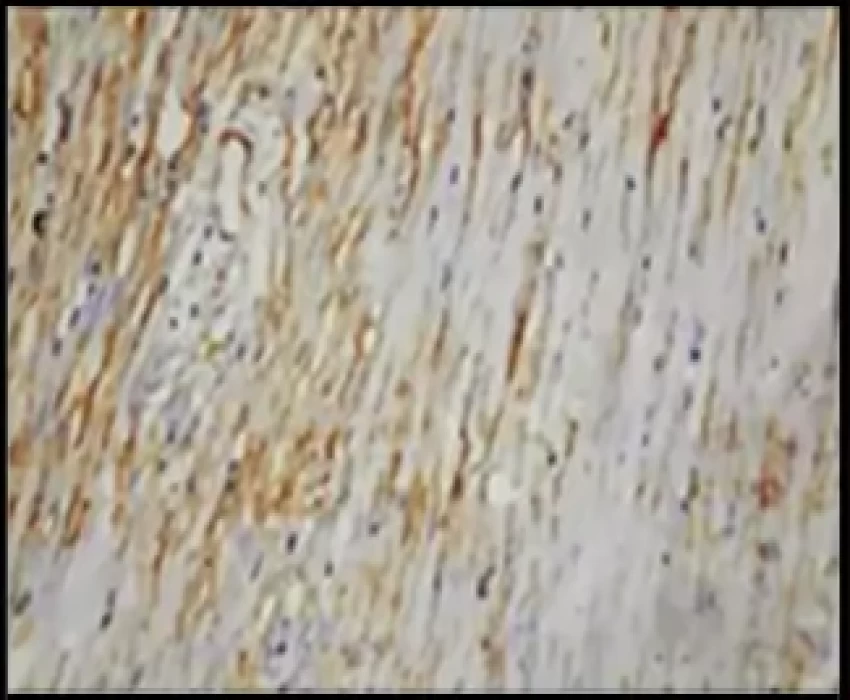

For the present study, twenty paraffin‑embedded tissue blocks each one of Dentigerous cyst (DC), KCOT, and Ameloblastoma were chosen. The diagnosis of tissues selected was confirmed through hematoxylin and eosin staining. Tissue sections were examined and interpretation for the number of myofibroblasts using α‑SMA immunostaining was done.

The result suggested that KCOT has the highest number of myofibroblasts, whereas DC showed the lowest. Among the groups, there were significant differences between the myofibroblast counts among DC and KCOT and between DC and ameloblastoma, whereas the difference in counts was not statistically significant between KCOT and ameloblastoma. A positive correlation was observed between the myofibroblast count and the known biological behavior of the lesions.